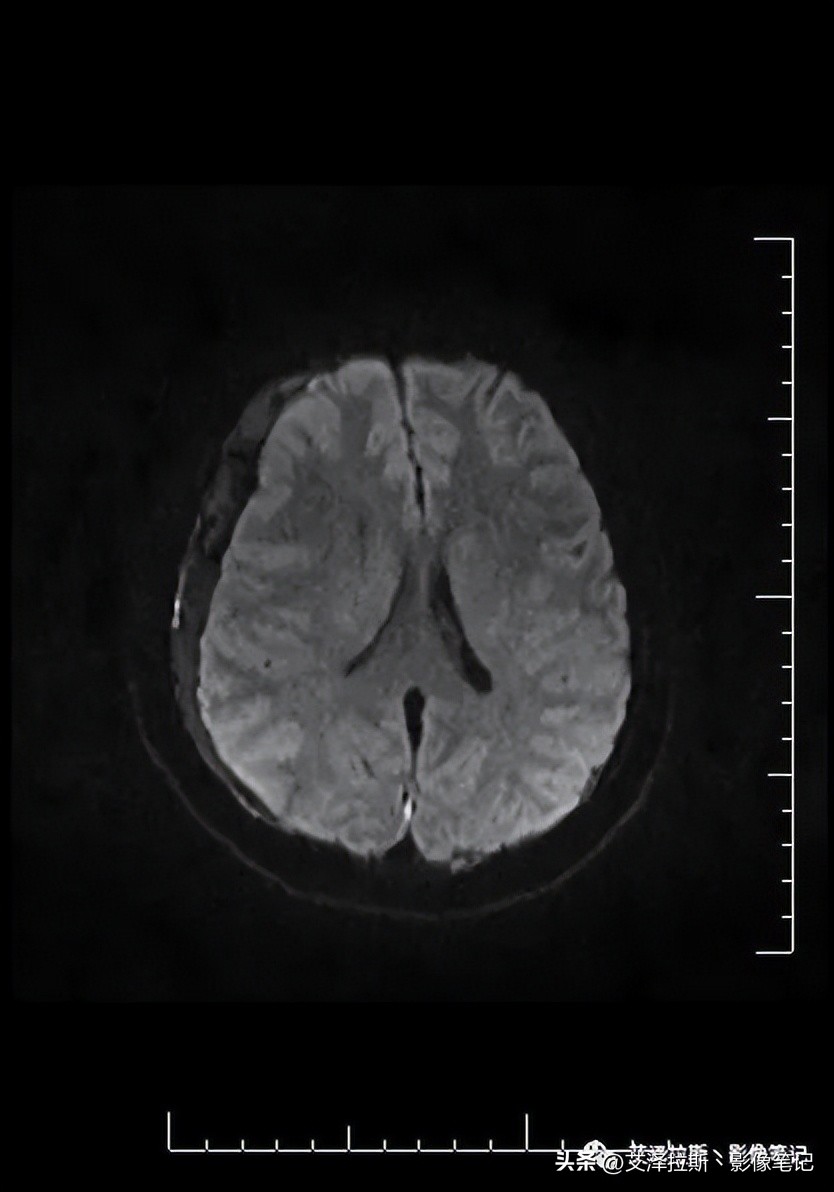

图4 DWI(b=1000s/mm²)

图1-4显示右侧硬膜下血肿(亚急性-慢性期)、大脑镰硬膜下血肿(亚急性期),小脑幕硬膜下血肿(未提供图片);图7-9显示硬脑膜增厚,明显均一强化,未见结节状强化,柔脑膜未见强化。

- 低颅压综合征;

- 右侧硬膜下血肿(亚急性-慢性期)、大脑镰硬膜下血肿、小脑幕硬膜下血肿(亚急性期)。